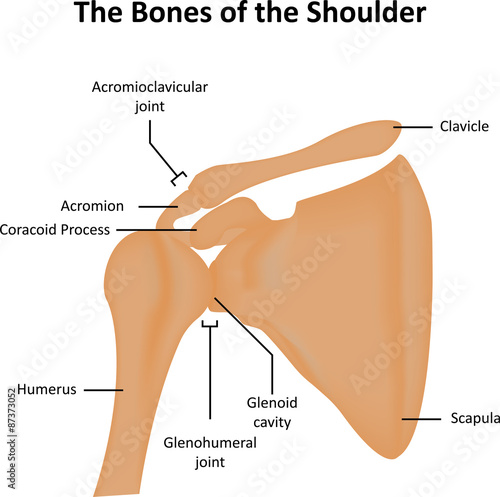

Glenohumeral ligament: анатомия и функции плечевого сустава